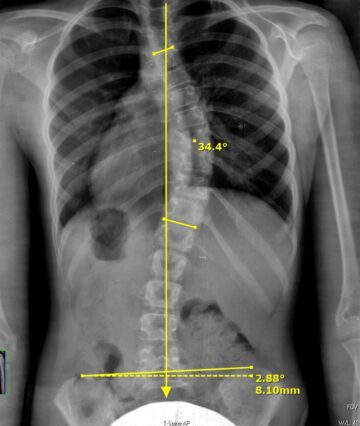

كيف يساعد الذكاء الاصطناعي في قياس زاوية كوب بدقة لتشخيص اعوجاج العمود الفقري؟ يُعد تشخيص اعوجاج العمود الفقري بدقة من أهم الخطوات لضمان علاج فعال وتقليل المضاعفات المستقبلية، ويُعتبر قياس زاوية كوب (Cobb Angle)

زاوية كوب لتشخيص اعوجاج العمود الفقري عند الأطفال والمراهقين | الدليل الطبي الشامل تحليل زاوية كوب (Cobb Angle) يُعد أداة أساسية في تشخيص مشكلات العظام، وخاصةً اعوجاج العمود الفقري (scoliosis). فمن خلال هذه الزاوية

كيف تساعد زاوية كوب في تشخيص اعوجاج العمود الفقري بدقة؟ تُعد زاوية كوب (Cobb Angle) المعيار الذهبي لقياس درجة انحناء العمود الفقري وتشخيص اعوجاج العمود الفقري المعروف باسم الجنف. كثير من المرضى أو أولياء